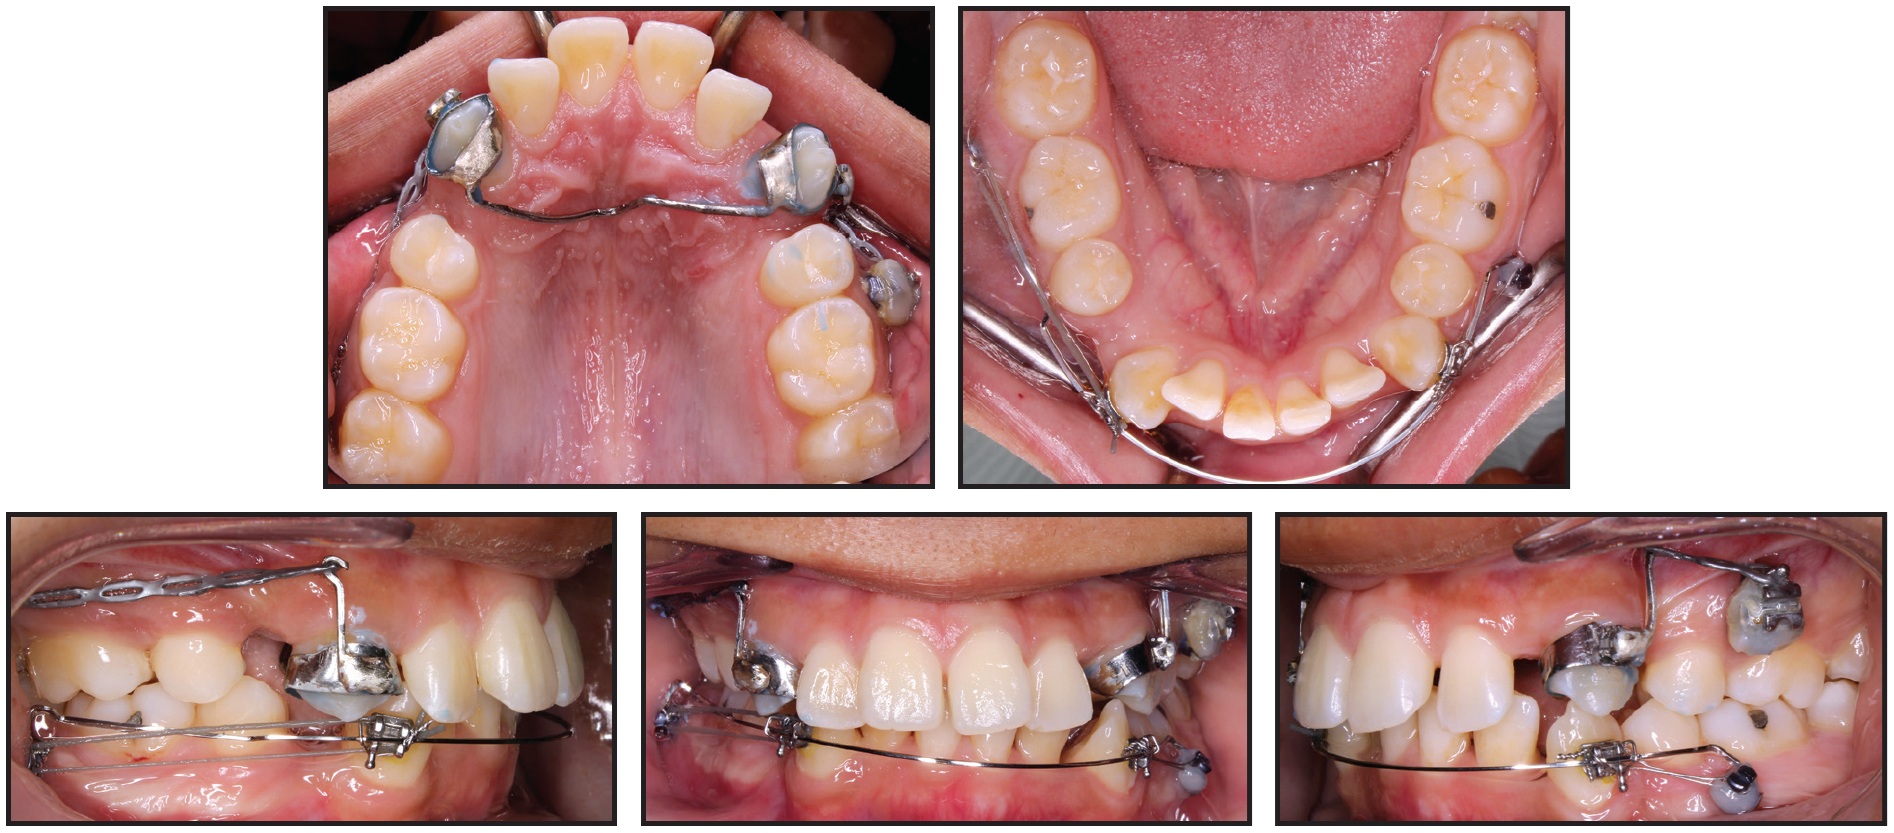

Both upper canines and the lower left canine were fully retracted after 20 months of treatment. At this stage, both arches were bonded with .022" preadjusted edgewise brackets, and mini-implants were removed (Fig. 6).

Fig. 6 Both arches bonded with .022" preadjusted edgewise brackets, mini-implants removed, and leveling and alignment initiated after 20 months of treatment.

Over four months of leveling and alignment, archwires progressed to .019" × .025" stainless steel in the maxilla and .017" × .025" beta titanium in the mandible. The residual spaces around the lower right canine and upper incisors were closed with light elastomeric chain, requiring another three months. Finishing bends were added during the last two months of treatment, but the patient wore no intermaxillary elastics for anchorage or finishing. After a total 27 months of treatment, appliances were removed and vacuum-formed retainers were delivered (Fig. 7A).

Fig. 7 A. Patient after 27 months of treatment.

Favorable dental and soft-tissue relationships were achieved, and the patient was pleased with the results. Both arches were well aligned; a Class I buccal occlusion was maintained on the right side, but the avoidance of intermaxillary elastics resulted in a slight loss of anchorage on the left side during final incisor retraction. The overjet was substantially reduced (from 7mm to 2mm), improving the lip position, smile esthetics, and profile. Cephalometric superimpositions indicated a slight decrease in the ANB angle and convexity (Fig. 7B).

Fig. 7 (cont.) B. Superimposition of pre- and post-treatment cephalometric tracings.

The upper incisors were substantially retracted, and the lower incisor inclination was reduced. There was improvement in the lip projection, especially the lower, in relation to the E-line (Table 1). The length of the roots—including those of the canines, which underwent active retraction for about 20 months—was basically unchanged from the initial radiograph (Table 2). Because the lower third molars showed significant mesial angulation, they were recommended for removal, along with the unopposed upper left third molar.